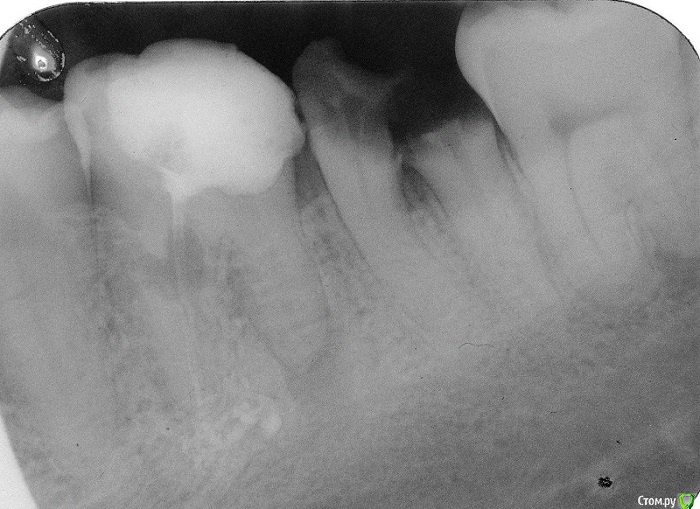

stomt Опубликовано 10 июня, 2018 Поделиться Опубликовано 10 июня, 2018 На скане видно корни левого крайнего нижнего моляра (перед зубом мудрости). Корни очевидно разошлись.Но мне важно чтобы не удалять этот зуб - возможно ли как то ортопедически соединить два корня, и сверху поставить коронку?Удалить мне нельзя - ибо я пользуюсь для жевание именно этим зубом, сверху ситуация еще хуже.Весной прошлого года, внутренняя стенка надщербилась и начала "колоть", врач сказала удалить хирургу лиш эту стенку, но через неделю-две вручную ее сама отломала, когда стенка начала шататся.Так что больше года даже эти корни еще годятся, хотя уже разошлись, и стираются до основания. Перед этим была большая пломба, которая быстро "отошла", но помагало наличие стенок..Возможно ли здесь поставить какие то штифты всередину корней, какие варианты сохранение жевательной функции этой части зубного ряда? Ссылка на комментарий

stomt Опубликовано 11 июня, 2018 Автор Поделиться Опубликовано 11 июня, 2018 На корнях что уже разошлись можно было вставить какие то штифты до расхождения? Мой врач год назад говорила что если корни целые то можно что то делать. Но она вряд ли имела ввиду уже пломбу если и год назад были одни корни и остатки стенки. Но даже так - что даже гипотетически невозможно ничего сделать с разошедшими корнями? Для меня как не специалиста - это как два отдельных однокореневых зуба. Может есть какие то специалисты что и за такие варианты с бифуркацией возьмутся? Ссылка на комментарий

red_butler Опубликовано 11 июня, 2018 Поделиться Опубликовано 11 июня, 2018 но для чего пишите удалять шестойпериодонтит, внутренняя резорбция и большая степень разрушения.Резюмируя: шестой, седьмой и восьмой зубы удалить. Установить два импланта и их протезировать. 3 1 Ссылка на комментарий

red_butler Опубликовано 12 июня, 2018 Поделиться Опубликовано 12 июня, 2018 И еще зуб мудрости вырвать. Для чего? для того, что бы не удалять его когда будут инсталлированы и протезированы импланты. Думал что мне здесь хотя предложать 6ой и 8ой использовать для замещение штучным зубом на месте 7ого? Или например использовать лиш 6ой для этого? Шестой удалять периодонтит, внутренняя резорбция и большая степень разрушения. Ссылка на комментарий